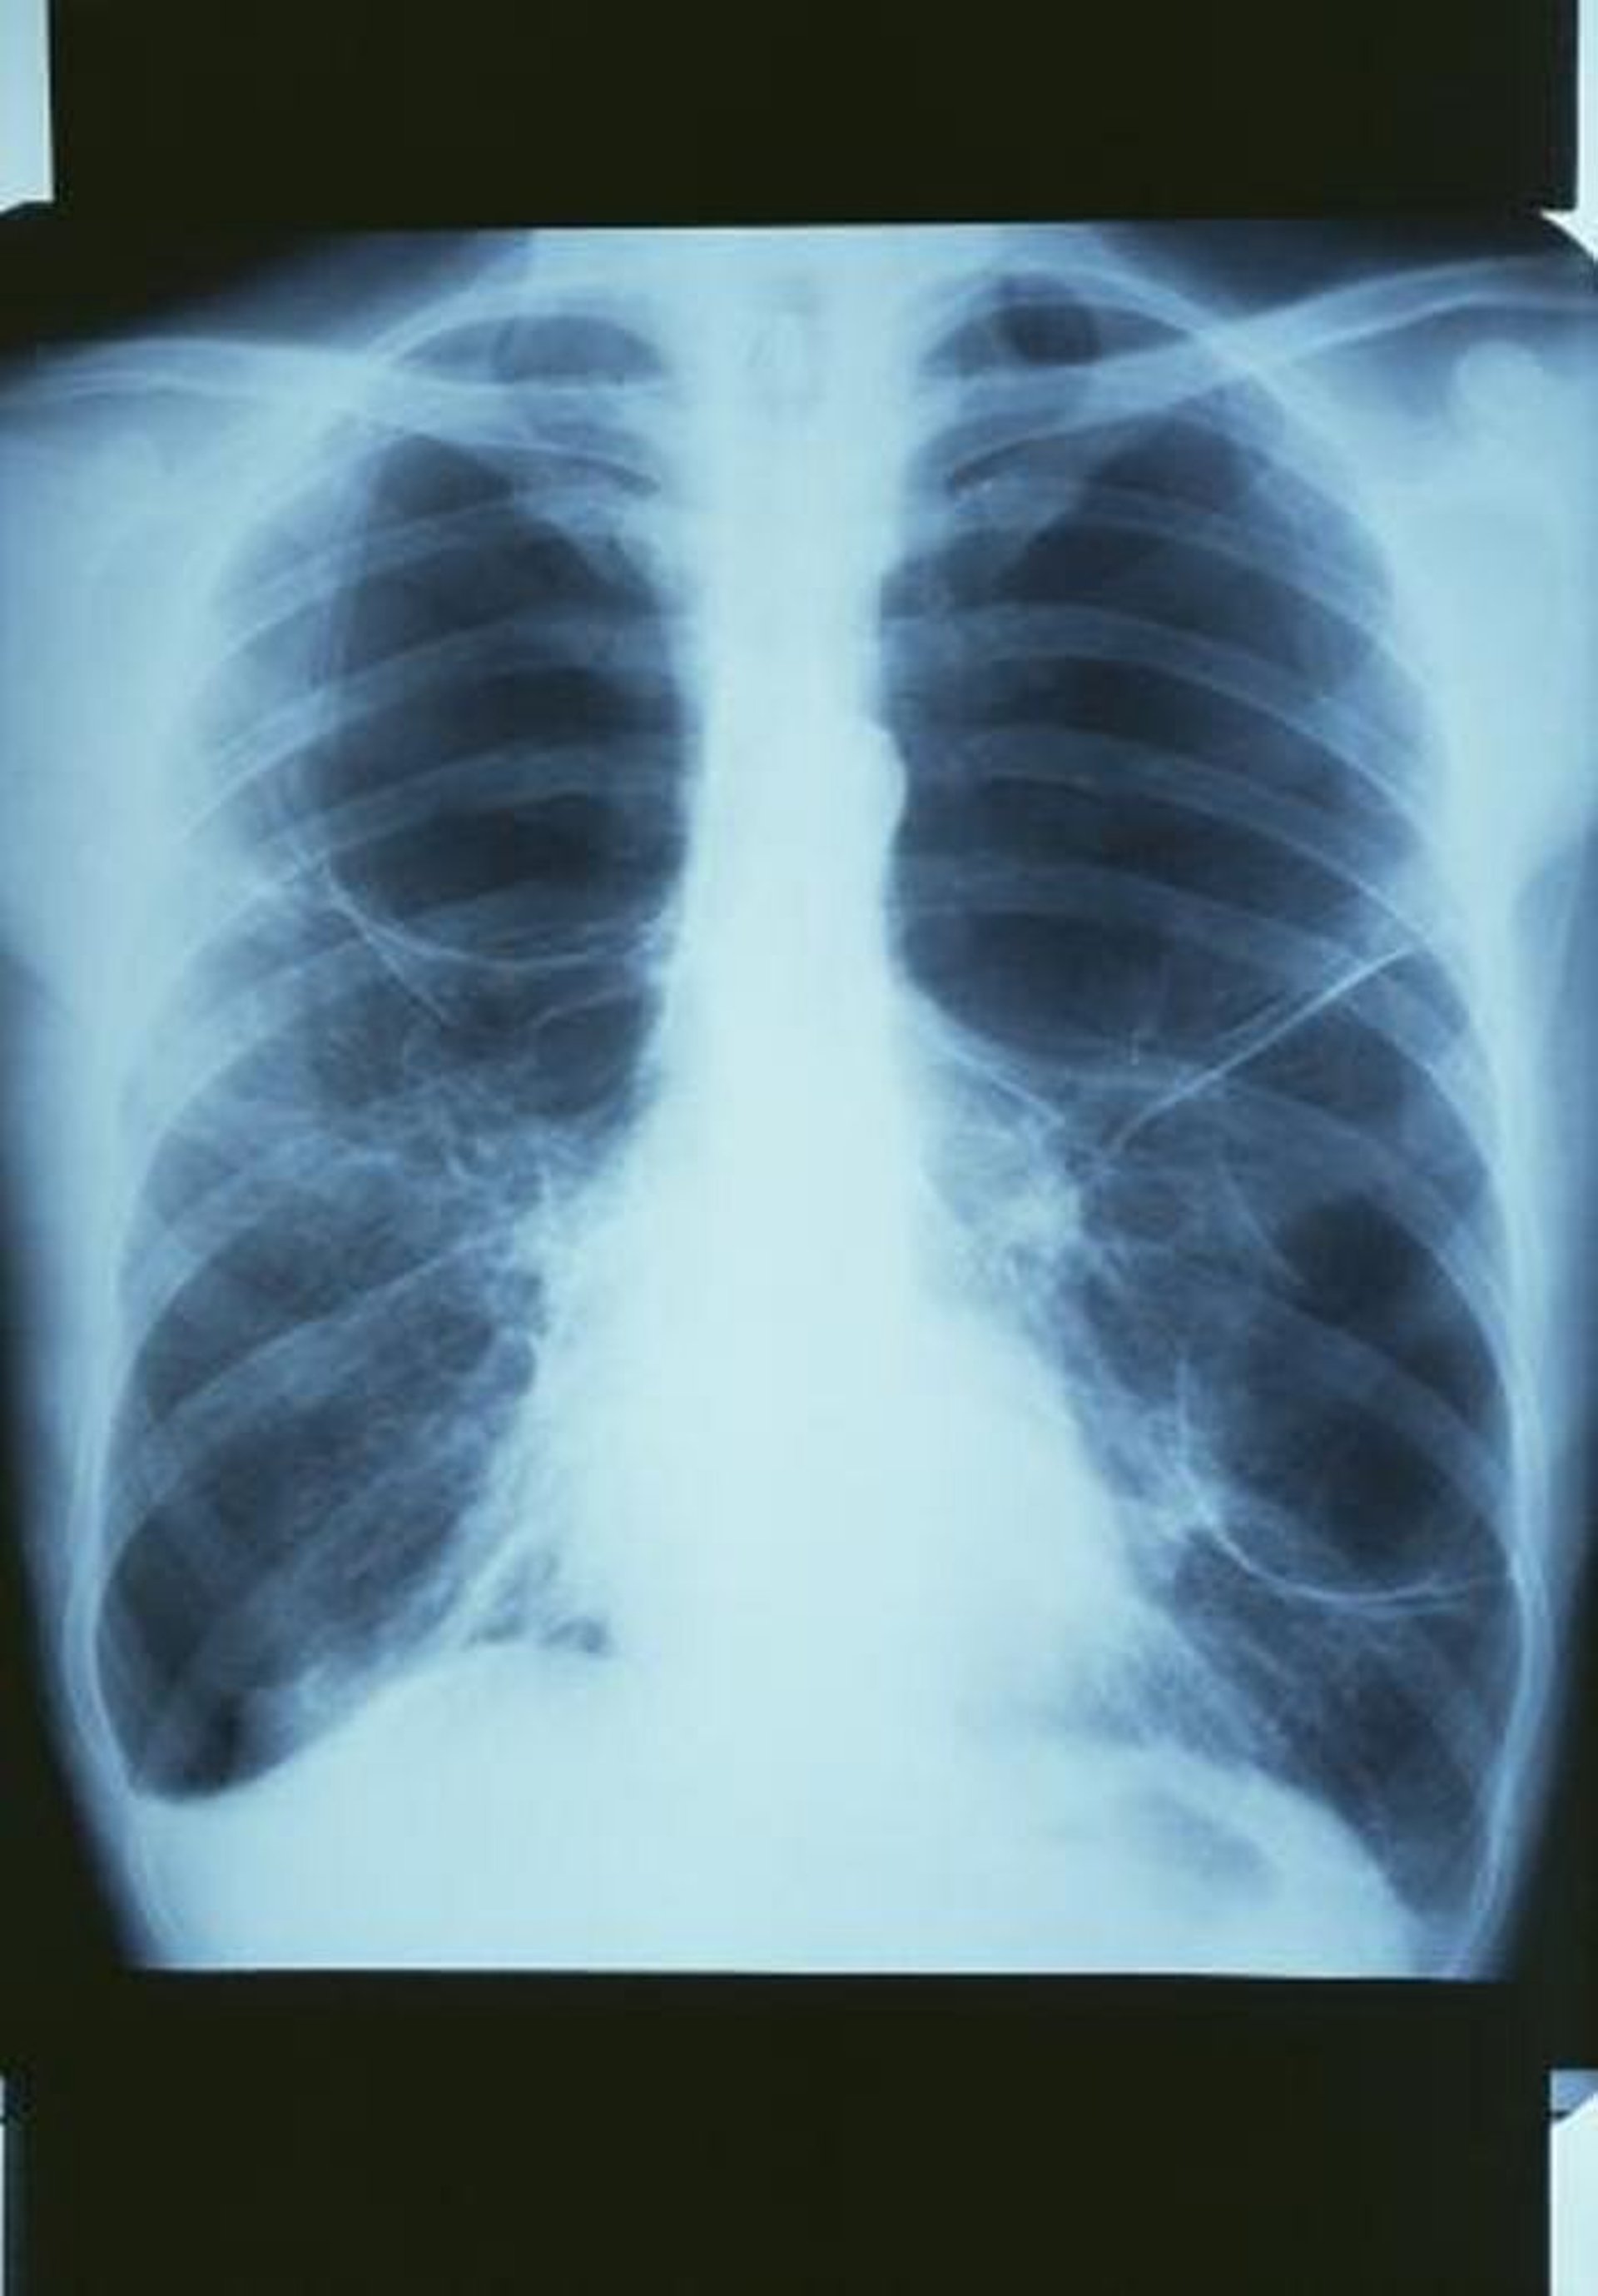

Bronchopneumopathies chroniques obstructives (BPCO) avec bulles

Cette radiographie thoracique montre une grande bulle dans le poumon supérieur droit et 2 grandes bulles dans le poumon gauche.

GJLP/CNRI/SCIENCE PHOTO LIBRARY